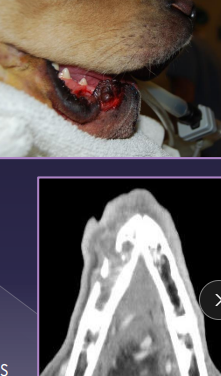

Oral Neoplasms

Et:

Dogs: Acanthomatous epulis, melanoma, SCC, fibrosarcoma, papilloma

Cats: SCC, fibrosarcoma

Dt: CT(extensive), FNA, Biopsy

Tx: Maxillectomy/mandibulectomy (CT first)

Consider eating ability, TMJ function, malocclusion, ulcerations